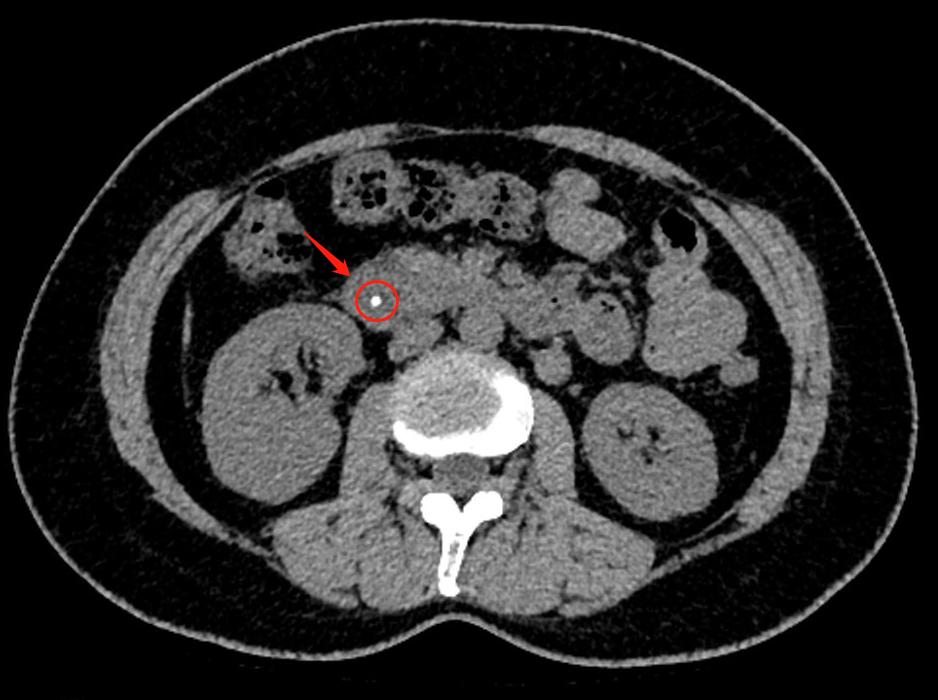

经过了CT检查,很快就找出了原因——胆总管卡着一颗大小约4mm的“石头”。这个石头卡在胆汁与胰液的出口处,让程女士出现腹痛。